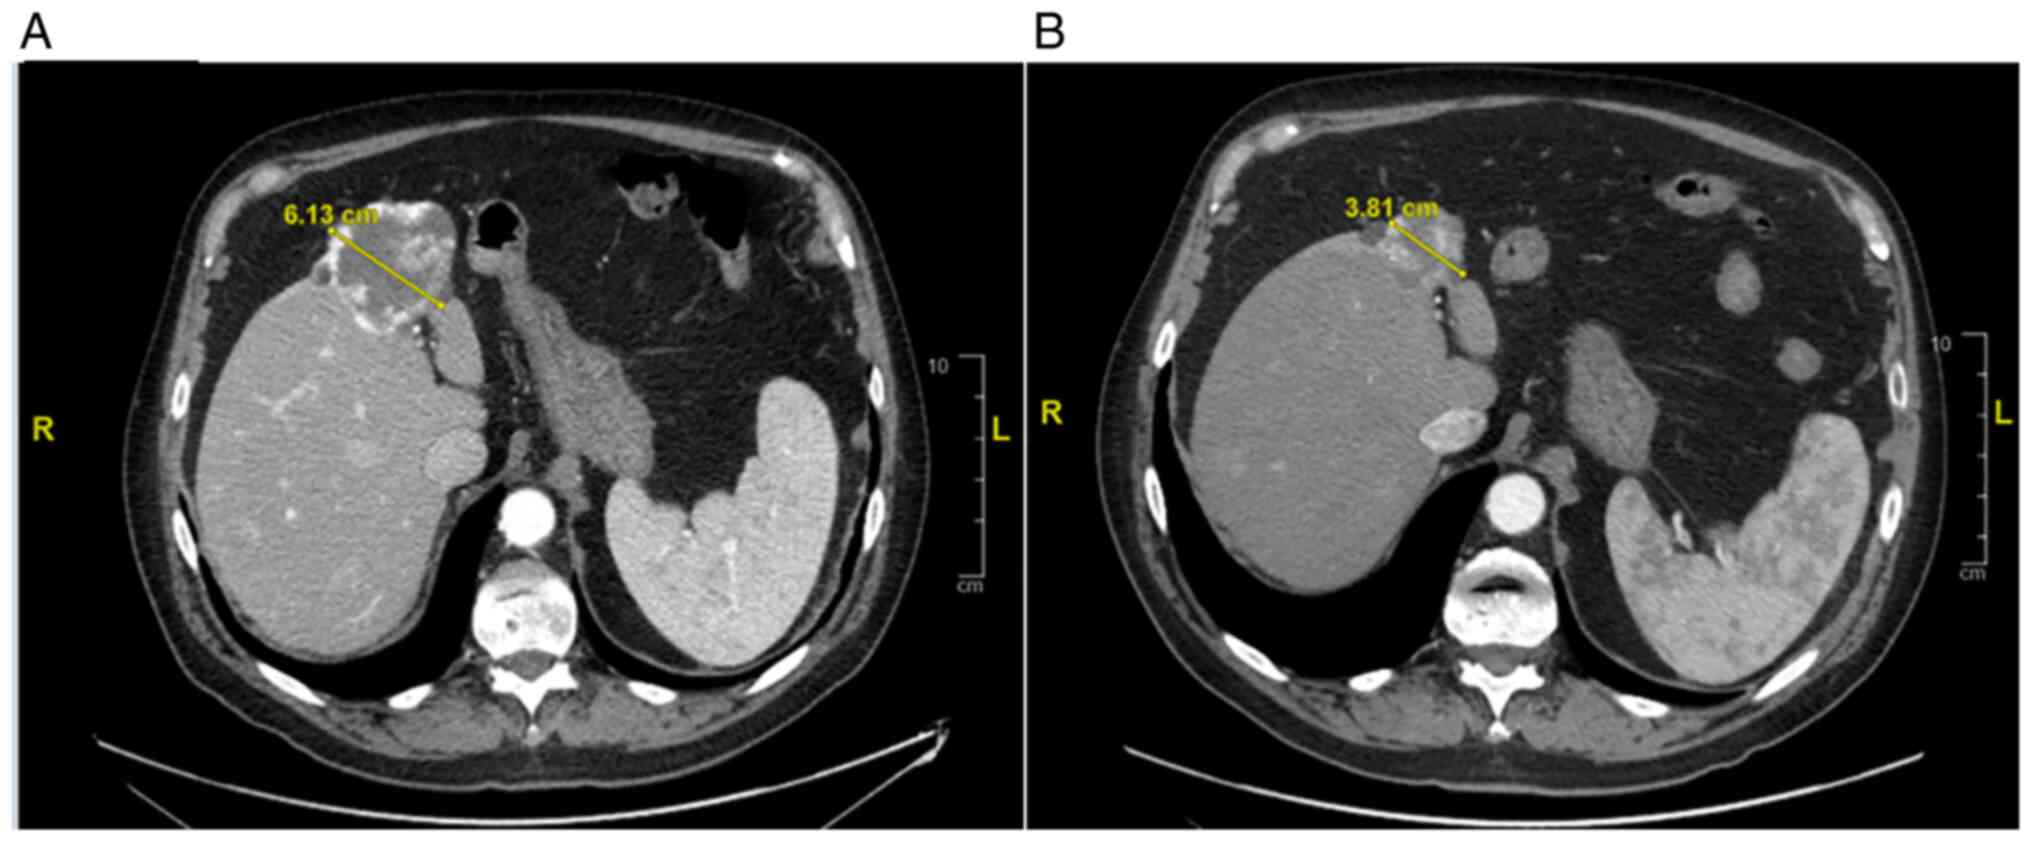

In September 2021, the patient repeated a total body CT-scan with the evidence of a strange behavior of the known liver lesion (dimensional reduction from 68 to 40 mm) Fig. 4.